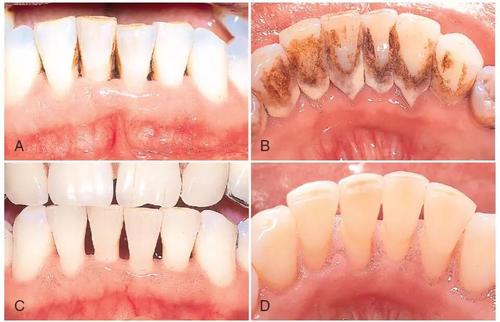

手动器械洗牙就是医务人员用洁牙工具将你牙齿中的软垢结石等一点点刮掉;超声波洗牙主要是通过超声波振动来清除顽固牙石;而喷沙洗牙是利用快速喷出的细盐微粒来清洗牙齿。

对于牙结石特别多的人有的医院会加收费用,因为结石多的人需要花更多的时间,有些一个半小时都洗不干净;而经常洁牙,牙周比较干净的一般四十分钟甚至更少时间可以搞定。

有些诊所是不做龈下洁治的,但是龈下其实更藏污纳垢一点,特别是没有洁过牙的,建议做一下龈下洁治。有些小诊所是因为不会所以不做龈下,只做龈上洁治的话,时间会更快,一般半小时左右就可以做完。

即使是洗牙这种最基本的操作,也需要找比较专业的口腔门诊或者医院,不当的操作有可能导致牙隐裂,而且洗牙后的抛光是必须的,抛光是将洁牙机在牙表面留下的划痕去掉,因为粗糙的平面比光滑的平面更容易堆积细菌。